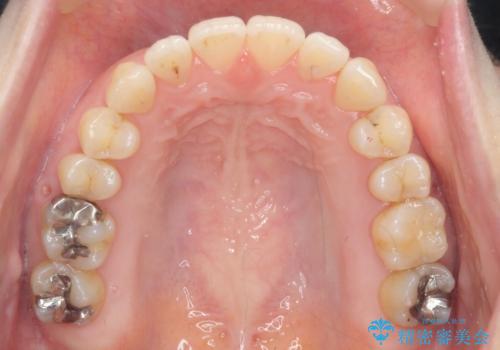

- 出っ歯に見える前歯を治したい、と矯正治療を希望され来院されました。

奥歯の噛み合わせに大きな問題はないので、目立つ前歯の角度・隙間を重点的に整え、審美的な歯並びを獲得できるよう計画します。

治療によりしっかりと前歯の角度が改善され、審美的な歯並びを手に入れることができました。